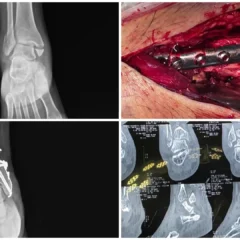

Clinical examination and imaging studies confirmed a Right Trimalleolar Ankle Fracture, involving:

-

Fibula (lateral malleolus)

-

Posterior malleolus

-

Medial malleolus

Such fractures disrupt ankle joint stability and require anatomical reduction for optimal recovery.

1️⃣ Open Reduction and Internal Fixation (ORIF)

Open reduction and internal fixation was performed for:

-

Fibula using plates and screws

-

Posterior malleolus using plates and screws

This ensured:

-

Accurate restoration of ankle alignment

-

Stable fixation of the lateral and posterior components

-

Proper joint congruity

2️⃣ Tension Band Wiring (TBW) for Medial Malleolus

The medial malleolus was stabilized using Tension Band Wiring (TBW) technique, which:

-

Converts tensile forces into compressive forces

-

Promotes stable bone healing

-

Provides strong fixation for small fracture fragments

The combined fixation approach restored full structural stability of the ankle joint.